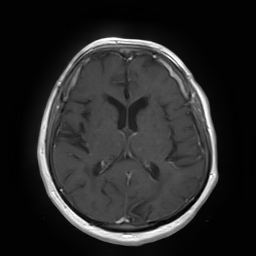

(a) Guide 𝑮𝑮\boldsymbol{G}

Refer to caption

(b) Input 𝑰𝑰\boldsymbol{I}

(c) Guidance map 𝑴𝑴\boldsymbol{M}

(d) Prediction 𝑷𝑷\boldsymbol{P}

(e) Ground truth

(f) Guide 𝑮𝑮\boldsymbol{G}

(g) Input 𝑰𝑰\boldsymbol{I}

(h) Guidance map 𝑴𝑴\boldsymbol{M}

(i) Prediction 𝑷𝑷\boldsymbol{P}

(j) Ground truth

Figure 2: Inputs and outputs of the guided filtering pipeline based on the WDSR network. T1 & T2 MRI pairs (a)-(e) and CT & MRI projection images (f)-(j).